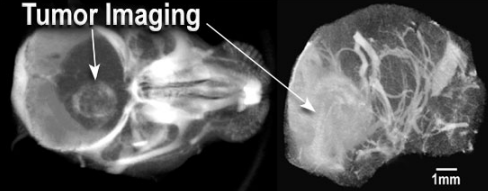

| |

| 靜脈注射AuroVist-15nm后活小鼠大腦的顯微CT: 左:由于AuroVist-15nm的穿透,腫瘤突出(白色)通過受損的血腦腫瘤屏障。 右:通過計算去除頭骨,顯示大腦血管系統(tǒng)。 | |